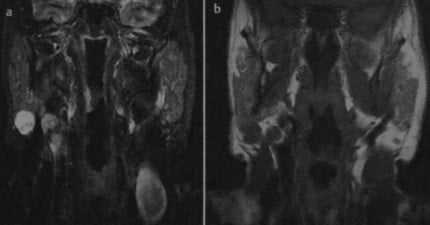

(Слева) На аксиальной МРТ (Т2 ВИ FS) в доле околоушной железы визуализируется гиперинтенсивная опухоль в с перегородками. Кистозную опухоль Уортина можно спутать с простой кистой.

(Справа) На аксиальной MPT (Т1 ВИ С+ FS) у этого же пациента визуализируется гипоинтенсивная опухоль с перегородками и контрастирующимся «ободком». Контрастирование помогает отличить опухоль Уортина от пропой костной кипы, но и позволяет прийти к ошибочному заключению о паротидном абсцессе. Обратите внимание на отсутствие уплотнения окружающей жировой клетчатки, что нетипично для абсцесса.2. КТ при опухоли Уортина:

![Снимки МРТ и КТ. Опухоль Уортина]()

Опухоль Уортина. Последовательность STIR, фронтальная проекция (а): гиперинтенсивное образование в нижней части правой околоушной железы. На Т1 -взвешенном изображении (b) образование гипоинтенсивно по отношению к железистой ткани.